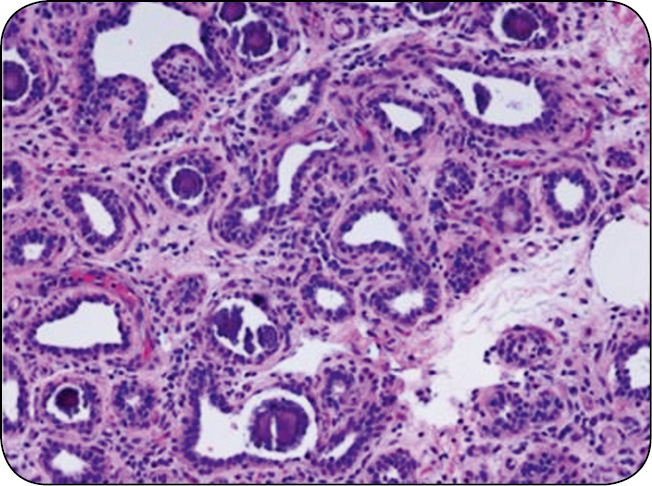

Czas od zakończenia laktacji do porodu to okres zasuszenia. U krowy trwa on przeważnie od 30 do 80 dni, zwykle 40-60 dni. W tym okresie poza przygotowaniem organizmu do zbliżającego się porodu tkanka gruczołu mlekowego ulega przemianom. Przebudowa tkanki wydzielniczej gruczołu mlekowego (inwolucja i ewolucja) odbywa się w trzech etapach. Pierwszy trwa 2-3 tygodnie i charakteryzuje się ograniczeniem zdolności komórek wydzielniczych do syntezy i sekrecji mleka oraz ich apoptozą. Druga faza – to trwający 3-4 tygodnie odpoczynek tkanki gruczołowej, kiedy ma miejsce pełne zasuszenie. W trzeciej fazie zachodzi ponowny rozwój tkanki wydzielniczej. W tej fazie, która przypada na ostatnie 2 tygodnie ciąży, nabłonek gruczołowy ulega proliferacji oraz dyferencjacji, czego konsekwencją jest produkcja siary, a po porodzie – mleka. W pierwszej i trzeciej fazie okresu zasuszenia, kiedy tkanka wymienia podlega intensywnej przebudowie, najczęściej dochodzi do zakażeń gruczołu mlekowego (ryc. 1, s. 43).